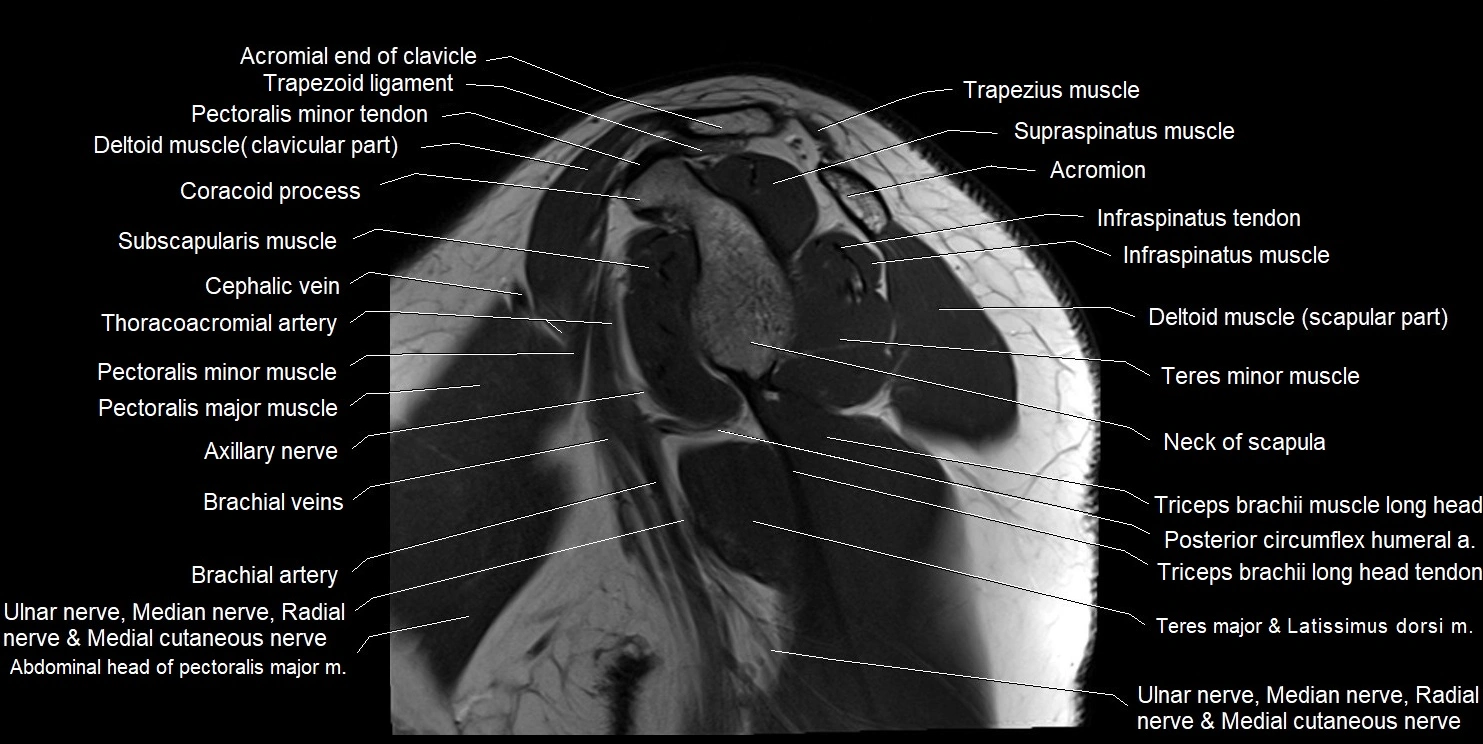

MRI images

image